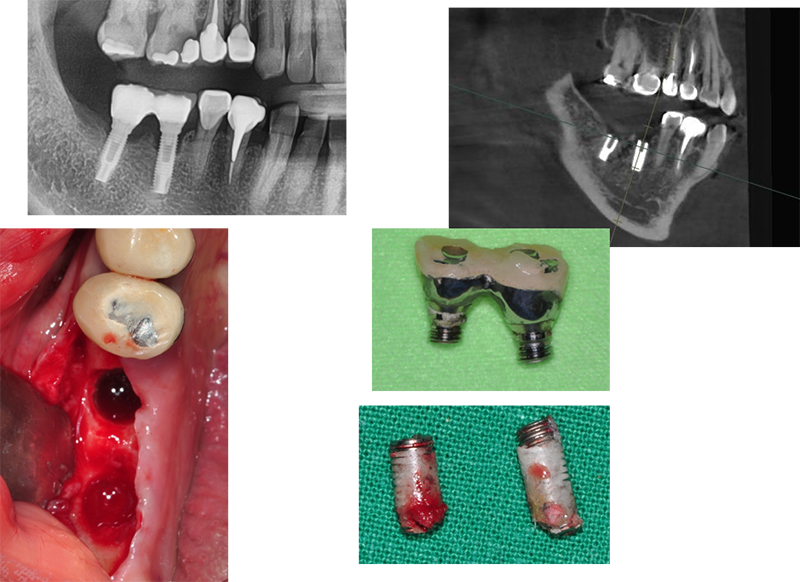

Bone loss

¿¡ µû¸¥ ÇȽºÃÄ ÆÄÀý

Ext. type 3.75mm Á÷°æÀÇ ÀÓÇöõÆ®.

Bruxism ÀÌ Àִ ȯÀÚ·Î½á ½É°í ±â´ÉÇÑ Áö 15³â ¸¸¿¡ ºÎ·¯Á®¼ ³»¿øÇß´Ù.

Á÷°æÀÌ 3.75mm·Î ¿¹Àü regular¿¡ ÇØ´çÇÏÁö¸¸ 4.0mmº¸´Ù ºÎ·¯Áö´Â °æ¿ì°¡ ¸¹´Ù.

¶ÇÇÑ ExtÀº º¸Ã¶ÀÌ ¿Ã¶ó°¡¸é Ç÷§Æû¿¡¼ 1.5mm °ñÈí¼ö°¡ °ÅÀÇ ÇÊ¿¬ÀûÀ¸·Î ÀϾÙ. À̹ø °æ¿ìµµ °ñÈí¼ö¿Í ±íÀº ¿¬°üÀÌ ÀÖ´Ù°í ¿©°ÜÁø´Ù.

¾Õ¿¡¼ ¾ê±âÇÑ °Íó·³ Á¦ÀÏ Áß¿äÇÑ °ÍÀº ¡°º¯ ¿¬°ñ Èí¼ö¡±°¡ ÀϾÁö ¸»¾Æ¾ß ÇÑ´Ù.

37¹ø 4.3 Á÷°æÀÇ ¿øÇöõÆ®

Á¦°ÅÇÏ´Ù°¡ ÈìÁýÀÌ ³¯ °Í °°¾Æ¼ Æ÷±âÇϰí

´ÙÀ½¿¡ ¾à¼Ó Àâ¾Ò´Âµ¥ ȯÀÚµµ Àúµµ ¹Ì·ç´Ù°¡ ÀÌ Áö°æµÊ.

ÆÄ³ë¶ó¸¶ »ó

°á±¹ ÇȽºÃÄ Á¦°Å

¾Æ¸¶µµ ±³ÇÕ¿¡ ¹®Á¦°¡ ÀÖ¾ú´ø µí

37¹ø abutment ÆÄÀý, µÚÂÊ¿¡ 8¹øÀÌ º¸À̰í, fixture Á÷°æÀÌ 5.0, Á¶±Ý ÈìÁýÀÌ ³ªµµ µÈ´Ù´Â »ý°¢À¸·Î Á¦°Å¼ö¼úÀ»

Çß´Ù.

3¹ø¿¡

³ª´²¼ °Ü¿ì Á¦°ÅÇÑ °æ¿ì